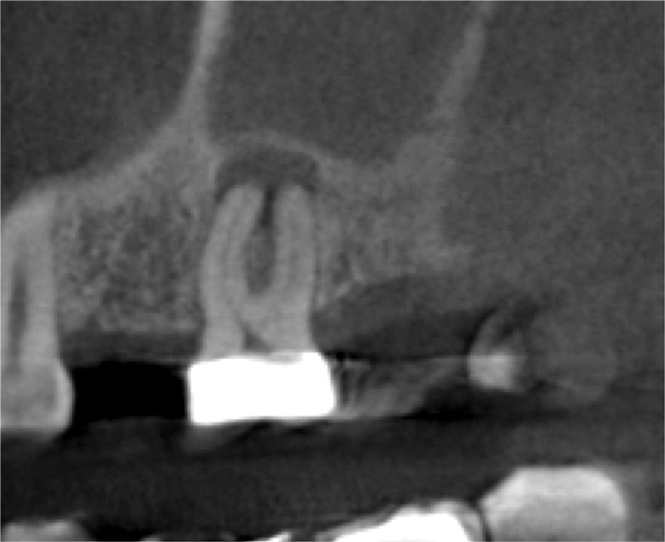

For patients suffering from MSEO, radiographs will reveal a periapical radiolucency with adjacent opacification in the maxillary sinus.12 Additional radiographic findings associated with MSEO include periapical mucositis and periapical osteoperiostitis (PAO). Periapical mucositis refers to mucosal thickening or dome-shaped soft-tissue expansion on the floor of the sinus directly adjacent to the infected root apex.PAO refers to the reactive osteogenesis caused by a local periosteal reaction that expands the sinus periosteum and displaces it upward into the sinus. It appears as a radiopaque "halo" surrounding the root apex (Figure 2 through Figure 4). PAO may be symptomatic and/or accompanied by adjacent mucosal edema and elevated sinus fluid levels.9 If left untreated, PAO can progress and result in a direct communication between the root apex and maxillary sinus.6,13 Unless bilateral odontogenic pathosis is found, the sinus opacifications will usually be unilateral and centered around the odontogenic source. Complete unilateral sinus opacifications may be missed on the CBCT images typically used in endodontics due to their limited or focused field of view (Figure 5). In cases involving complete unilateral sinus opacification, referral to an ENT or oral surgeon is essential to rule out invasive fungal infection or malignancy.2,17,24

(4.) Coronal slice of CBCT image of the same tooth.

Figure 4